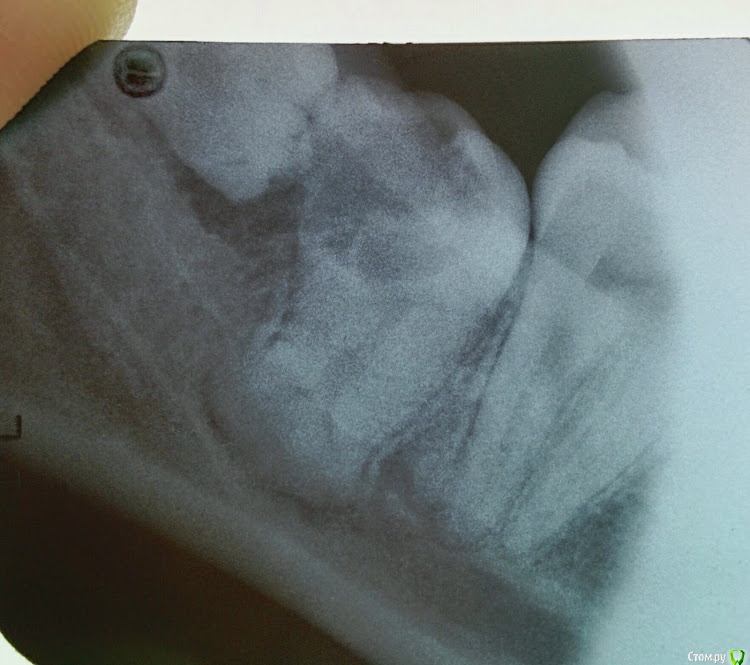

Kovalov Igor Опубликовано 26 марта, 2015 Поделиться Опубликовано 26 марта, 2015 48 и 49 зуб... пошел на удаление 48, откинул лоскут а там 49))) сделал потом Rg.49 вышел очень быстро, а 48 нет)) 7 Ссылка на комментарий

red_butler Опубликовано 26 марта, 2015 Поделиться Опубликовано 26 марта, 2015 сделал потом Rg снимки нужно делать до... 1 1 Ссылка на комментарий

Kovalov Igor Опубликовано 26 марта, 2015 Поделиться Опубликовано 26 марта, 2015 снимки нужно делать до... Ну там с виду обычная восьмерка была. Думаю Вы тоже не всегда делаете Rg при удалении ... Или ошибаюсь ? Ссылка на комментарий

Kev Опубликовано 26 марта, 2015 Поделиться Опубликовано 26 марта, 2015 Ну там с виду обычная восьмерка была. Думаю Вы тоже не всегда делаете Rg при удалении ... Или ошибаюсь ?8ки зубы-сюрпризы, так что всегда Rg делаю=))Хотя рентген тоже не панацея=)) Ссылка на комментарий

red_butler Опубликовано 26 марта, 2015 Поделиться Опубликовано 26 марта, 2015 Ну там с виду обычная восьмерка была. Думаю Вы тоже не всегда делаете Rg при удалении ... Или ошибаюсь ?у меня ОПГ обязательный элемент диагностики 3 Ссылка на комментарий

Kovalov Igor Опубликовано 27 марта, 2015 Поделиться Опубликовано 27 марта, 2015 у меня ОПГ обязательный элемент диагностикихороший подход, просто снимок прицельный у нас делают так, что видна только коронка, верхушек корней 8ых зубов не видать и подавно, оптг другое дело) 1 Ссылка на комментарий